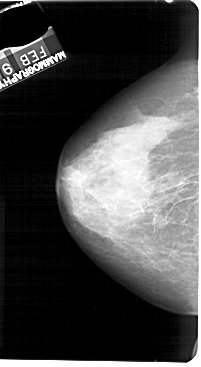

A_1270_1.LEFT_CC

LEFT_CC LINES 5491 PIXELS_PER_LINE 3001 BITS_PER_PIXEL 12 RESOLUTION 43.5 NON_OVERLAY